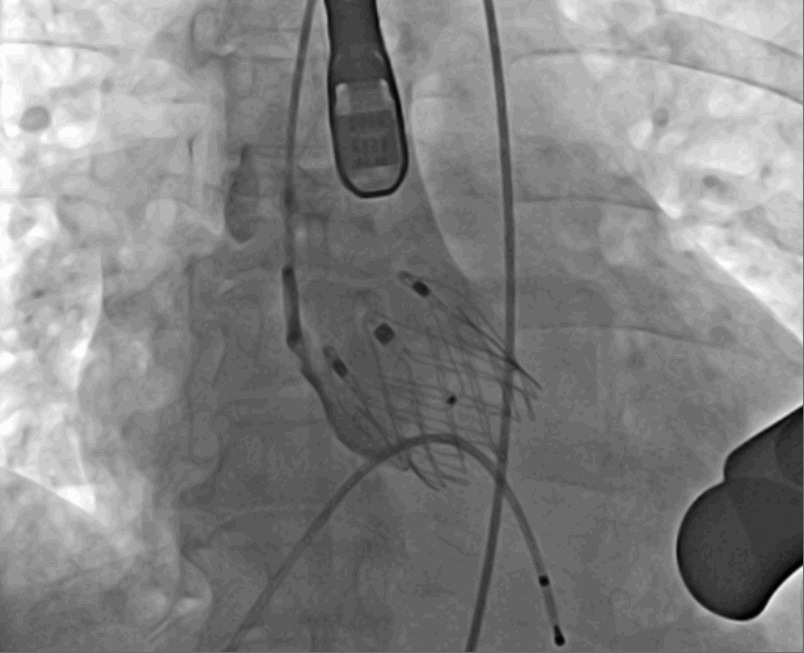

手術(shù)采用經(jīng)心尖入路,對患者進(jìn)行全麻后,在左側(cè)心尖處做3-4cm微創(chuàng)手術(shù)切口,在DSA及超聲引導(dǎo)下手術(shù)順利完成。從導(dǎo)入器械到完成瓣膜置入,僅耗時約10分鐘。術(shù)后即刻主動脈瓣返流程度由術(shù)前大量返流轉(zhuǎn)為消失,患者于導(dǎo)管室拔除氣管插管,次日由ICU轉(zhuǎn)入普通病房。

術(shù)中釋放定位鍵后DSA影像圖